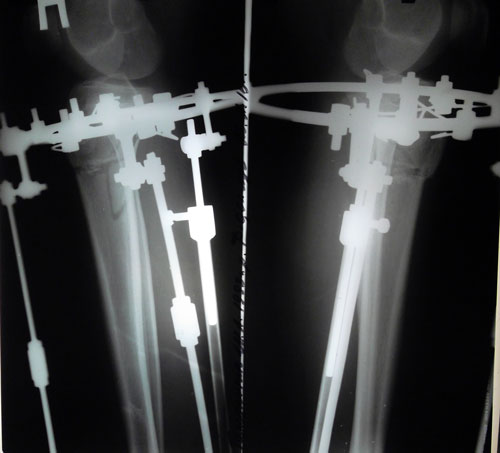

Дата операции 03.11.2015г.

Дата снятия 08.01.2016г.

Срок лечения 65 дней.